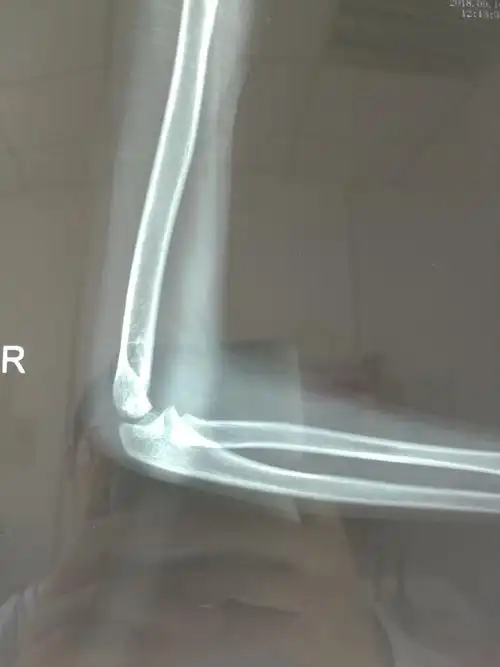

如此严重的肱骨远端粉碎骨折,还能治好吗?

儿童肱骨远端粉碎性骨折治疗 [病例帖]

右肱骨远端粉碎骨折切开复位内固定术